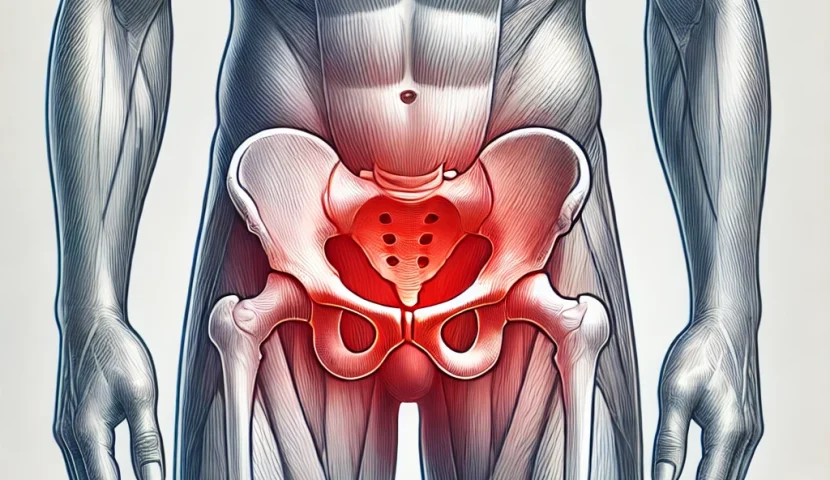

グロインペイン症候群とは?

グロインペイン症候群とは、主に鼠径部(股関節周辺)に痛みが生じるスポーツ障害の一種です。特に、急な方向転換や蹴り動作を多用する競技の選手に多く発生します。初期は軽い違和感から始まりますが、悪化すると痛みが強くなり、プレーに支障をきたすこともあります。

主な原因

この症状の原因として、以下のようなものが考えられます。

- 股関節周囲の筋肉への過剰な負担

- 姿勢の乱れや柔軟性の低下

- オーバーユース(使いすぎ)による筋肉や腱の疲労

- 正しくないフォームや動作の繰り返し

特に、日頃のケアを怠ると症状が悪化しやすくなるため、注意が必要です。